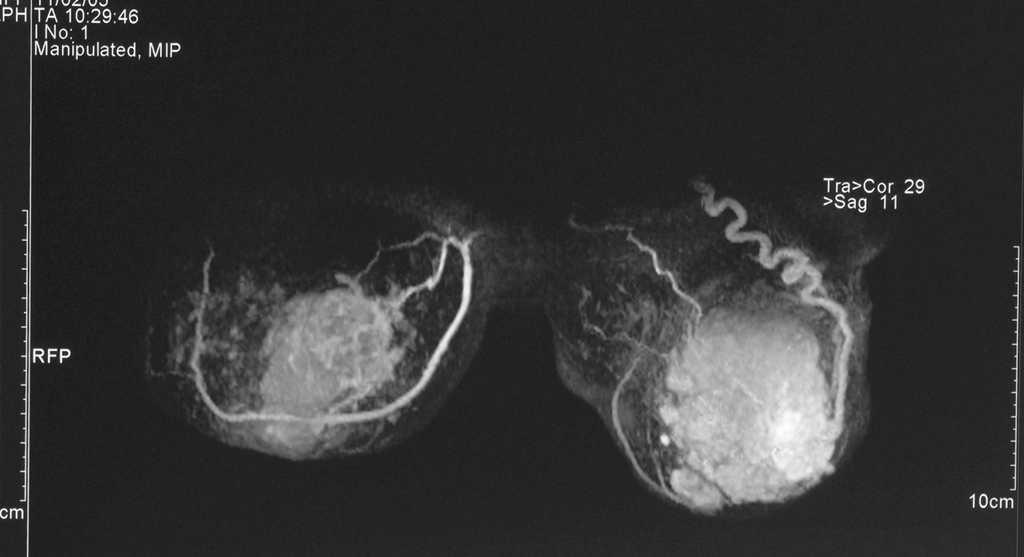

Antes de realizar la biopsia de ambas mamas, se realizó una mamografía, una ecografía y una resonancia magnética bilateral (figs. 1-4). Tras obtener y analizar las imágenes, se procedió a una punción con aguja gruesa, tanto del nódulo en el CSE de la MD como del área de aumento de densidad en los cuadrantes externos de la MI. El nódulo de la MD se describió como CDI (fig. 5) y la biopsia de la MI informó de la presencia de áreas de CLI (fig. 6). Los receptores de estrógenos (RE) y de progesterona (RP) eran negativos en la MD y el tumor no sobreexpresaba la proteína Her2. El tumor de la MI presentaba RE (+), RP () y sobreexpresaba Her2. Se realizó un estudio de extensión que fue negativo para lesiones metastásicas.

Figura 3. Resonancia magnética bilateral inicial. MD: mama derecha; MI: mama izquierda.

Figura 4. Resonancia magnética bilateral inicial; proyección en 3D. En la mama derecha se observa una masa irregular, de márgenes mal delimitados (1). En la mama izquierda se aprecia una masa polilobulada, algo más grande, que ocupa la totalidad de los cuadrantes externos (2).